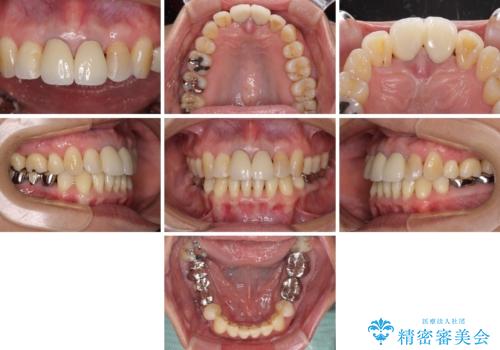

部分矯正とセラミック 前歯の審美治療

- 上の前歯の変色と、下の前歯のデコボコを気にして来院された患者様です。

前歯はオールセラミッククラウンに補綴することとしました。

補綴治療に先立ち、下顎前歯の部分矯正を行い、前歯の咬み合わせの安定性向上を図りました。

当初は上顎の補綴治療のみを希望されていましたが、奥歯にブリッジなど補綴物が多くあり、前歯も変色しているため、治療費が高額となってしまうことが懸念されました。

相談の上、最も気になっている前歯の部分矯正と補綴治療により口元の改善を図ることとしました。

審美面と合わせて清掃性も改善され、患者様には大変満足していただきました。